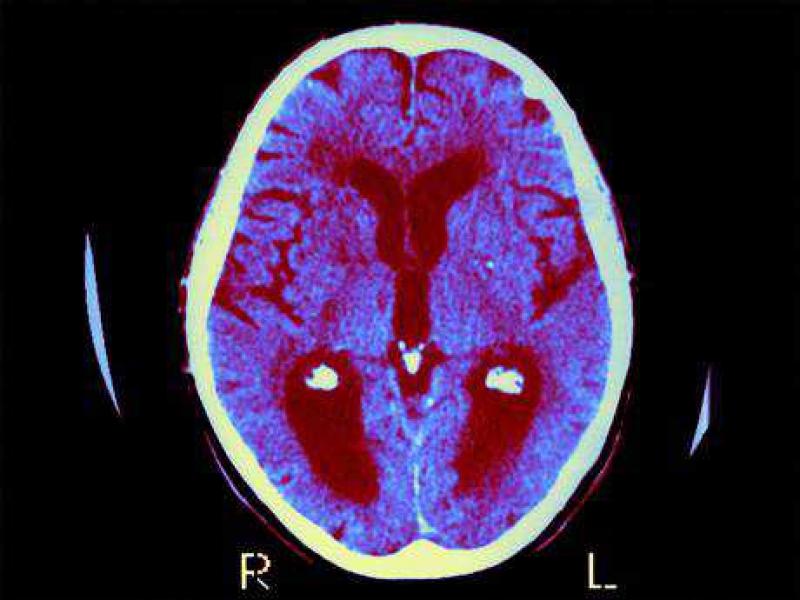

De onderzoekers vonden dat immuniteitscellen die normaal het brein beschermen in plaats daarvan een essentiële voedingsstof genaamd arginine beginnen verbruiken. Door dat proces te blokkeren met een geneesmiddel, konden zij de vorming van amyloïde plaques in de hersenen die kenmerkend zijn voor de ziekte van Alzheimer, voorkomen en ook het geheugenverlies bij muizen stoppen.

Carol Colton, hoogleraar neurologie aan de Duke University en auteur van de nieuwe studie, zei dat het onderzoek naar Alzheimer gedomineerd werd door pogingen om de rol van amyloïde te begrijpen, dat is het eiwit dat zich opstapelt in de hersenen om plaques te vormen, maar dat aandacht voor arginine en het immuunsysteem nieuwe ontdekkingen kan opleveren.